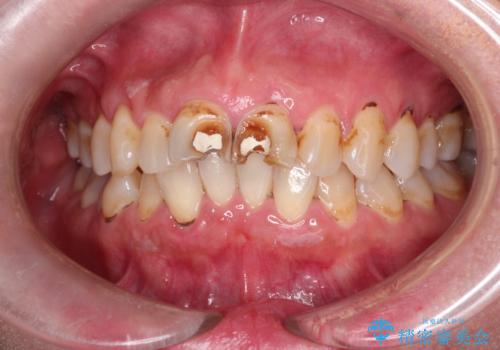

[ セラミック治療 ] 虫歯でつぎはぎになってしまった歯をきれいにしたい

担当医 大元洋佑

![[ セラミック治療 ] 虫歯でつぎはぎになってしまった歯をきれいにしたいの症例 治療前](https://seimitsushinbi.jp/wp/wp-content/uploads/2023/11/97b046ffd9b5b3b60d51f437c4943149-500x350.jpg?v=1700791880)

![[ セラミック治療 ] 虫歯でつぎはぎになってしまった歯をきれいにしたいの症例 治療後](https://seimitsushinbi.jp/wp/wp-content/uploads/2023/11/e5fb48a77a0a81d51a52e838569890a9-500x350.jpg?v=1700791903)